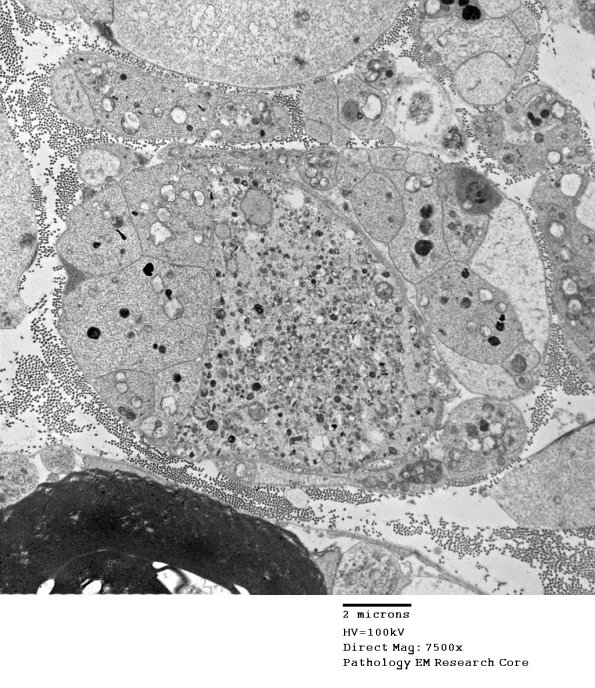

Variation in content between regenerating growth cones is seen at higher magnification in 3B7A,B. (electron micrographs)